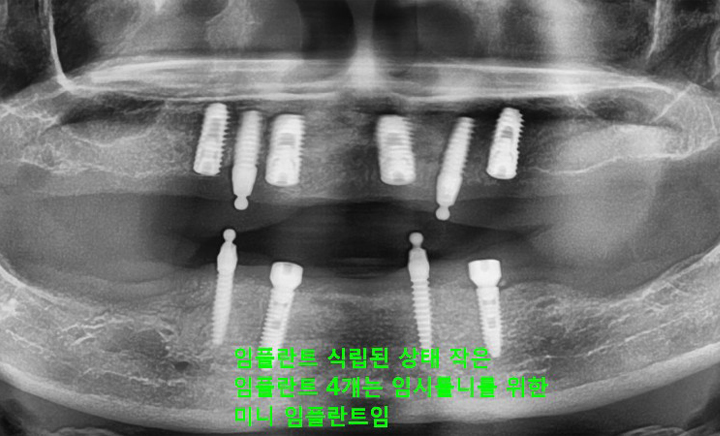

환자분 상태에 따라 임플란트를 2개에서 4개 정도만을 식립하고

그 위에 틀니를 고정시키는 치료 방법

CASE #1